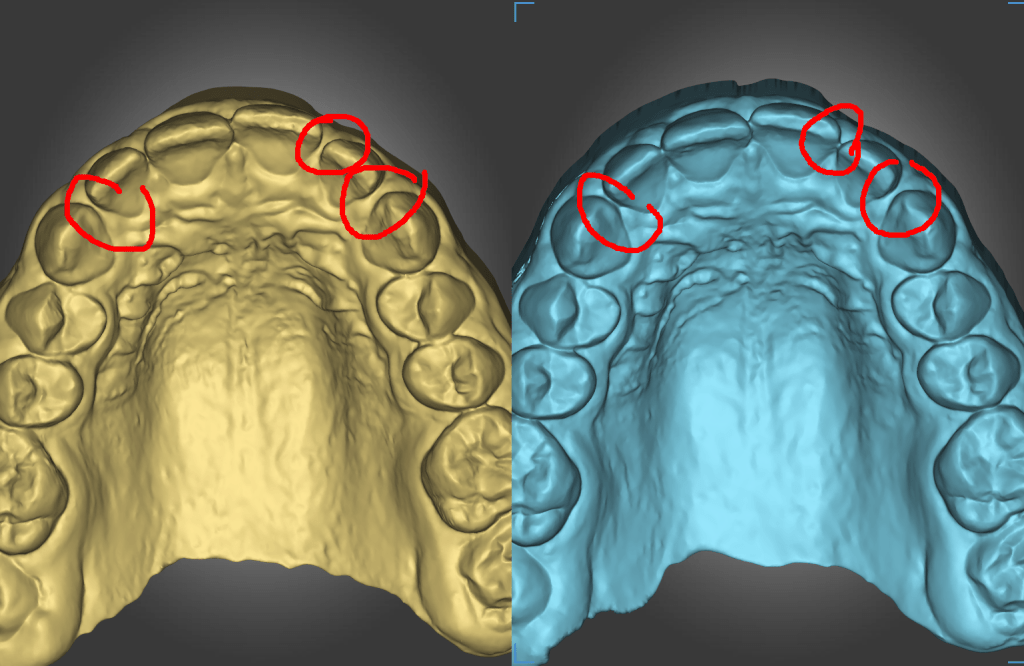

Mackenzie. L – Myobrace – Age 9

Adaptive Orthodontics TREATMENT STARTED AT AGE : 9 Myobrace K1 MediumMixed DentitionClass 2 Div IModerate 1st Review – 2023-03-01 YELLOW = Initial 2022-10-29 BLUE = 1st Review 2023-03-01 Compliance was not good in the first quarter. Not much expansion seen on buccal side 2nd Review – 2023-05-30 YELLOW = Initial 2022-10-29 BLUE = 2nd Review2023-05-30… Read.